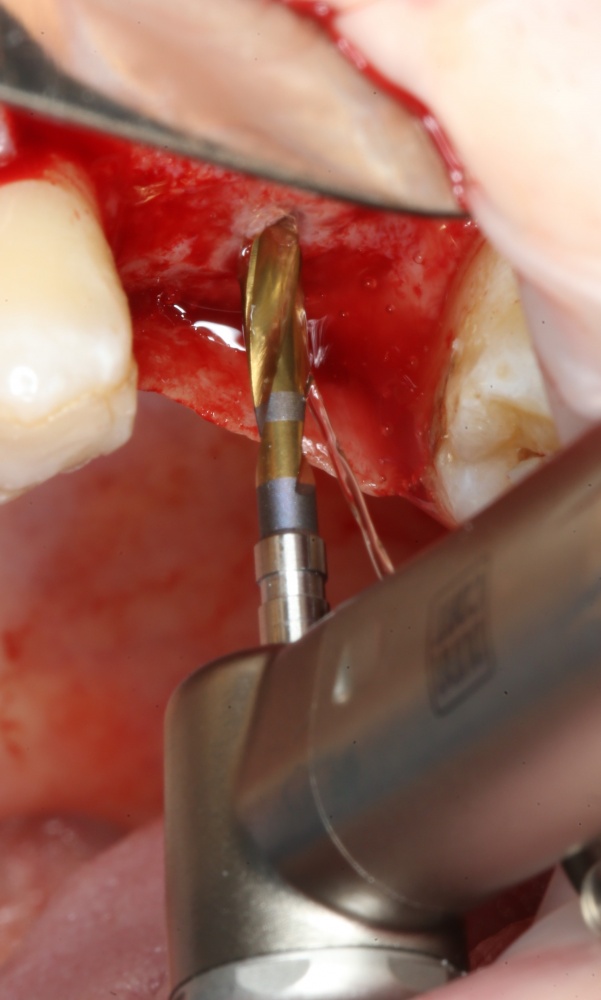

Следующей мы используем фрезу 2.0/3.2:

Такие фрезы — особенность имплантационной системы Astra Tech. Они нужны для того, чтобы не разломать края лунки и сделать переход между фрезами (а мы переходим с 2.0 на 3.2 мм) более точным и плавным, благодаря направляющей 2.0 мм. Однако, пройти лунку такой фрезой на всю глубину удаётся далеко не всегда. В таких случаях используется обычная спиральная фреза диаметром 3.2 мм (с зеленой полоской). Но в нашем случае такой необходимости нет, ибо выше только субантральное пространство, поэтому мы работаем только вот такой двойной фрезой.

Если бы мы хотели поставить имплантат диаметром 4.5 мм, то далее мы перешли бы к кортикальной конической фрезе. Однако ж, я посчитал, имплантат диаметром 5.0 мм в данной клинической ситуации будет более надежным и органичным, поэтому мы продолжаем подготовку лунки. И следующая используемая фреза — 3.2/3.7 — то же самое. что и предыдущая, с направляющей 3.2 мм: